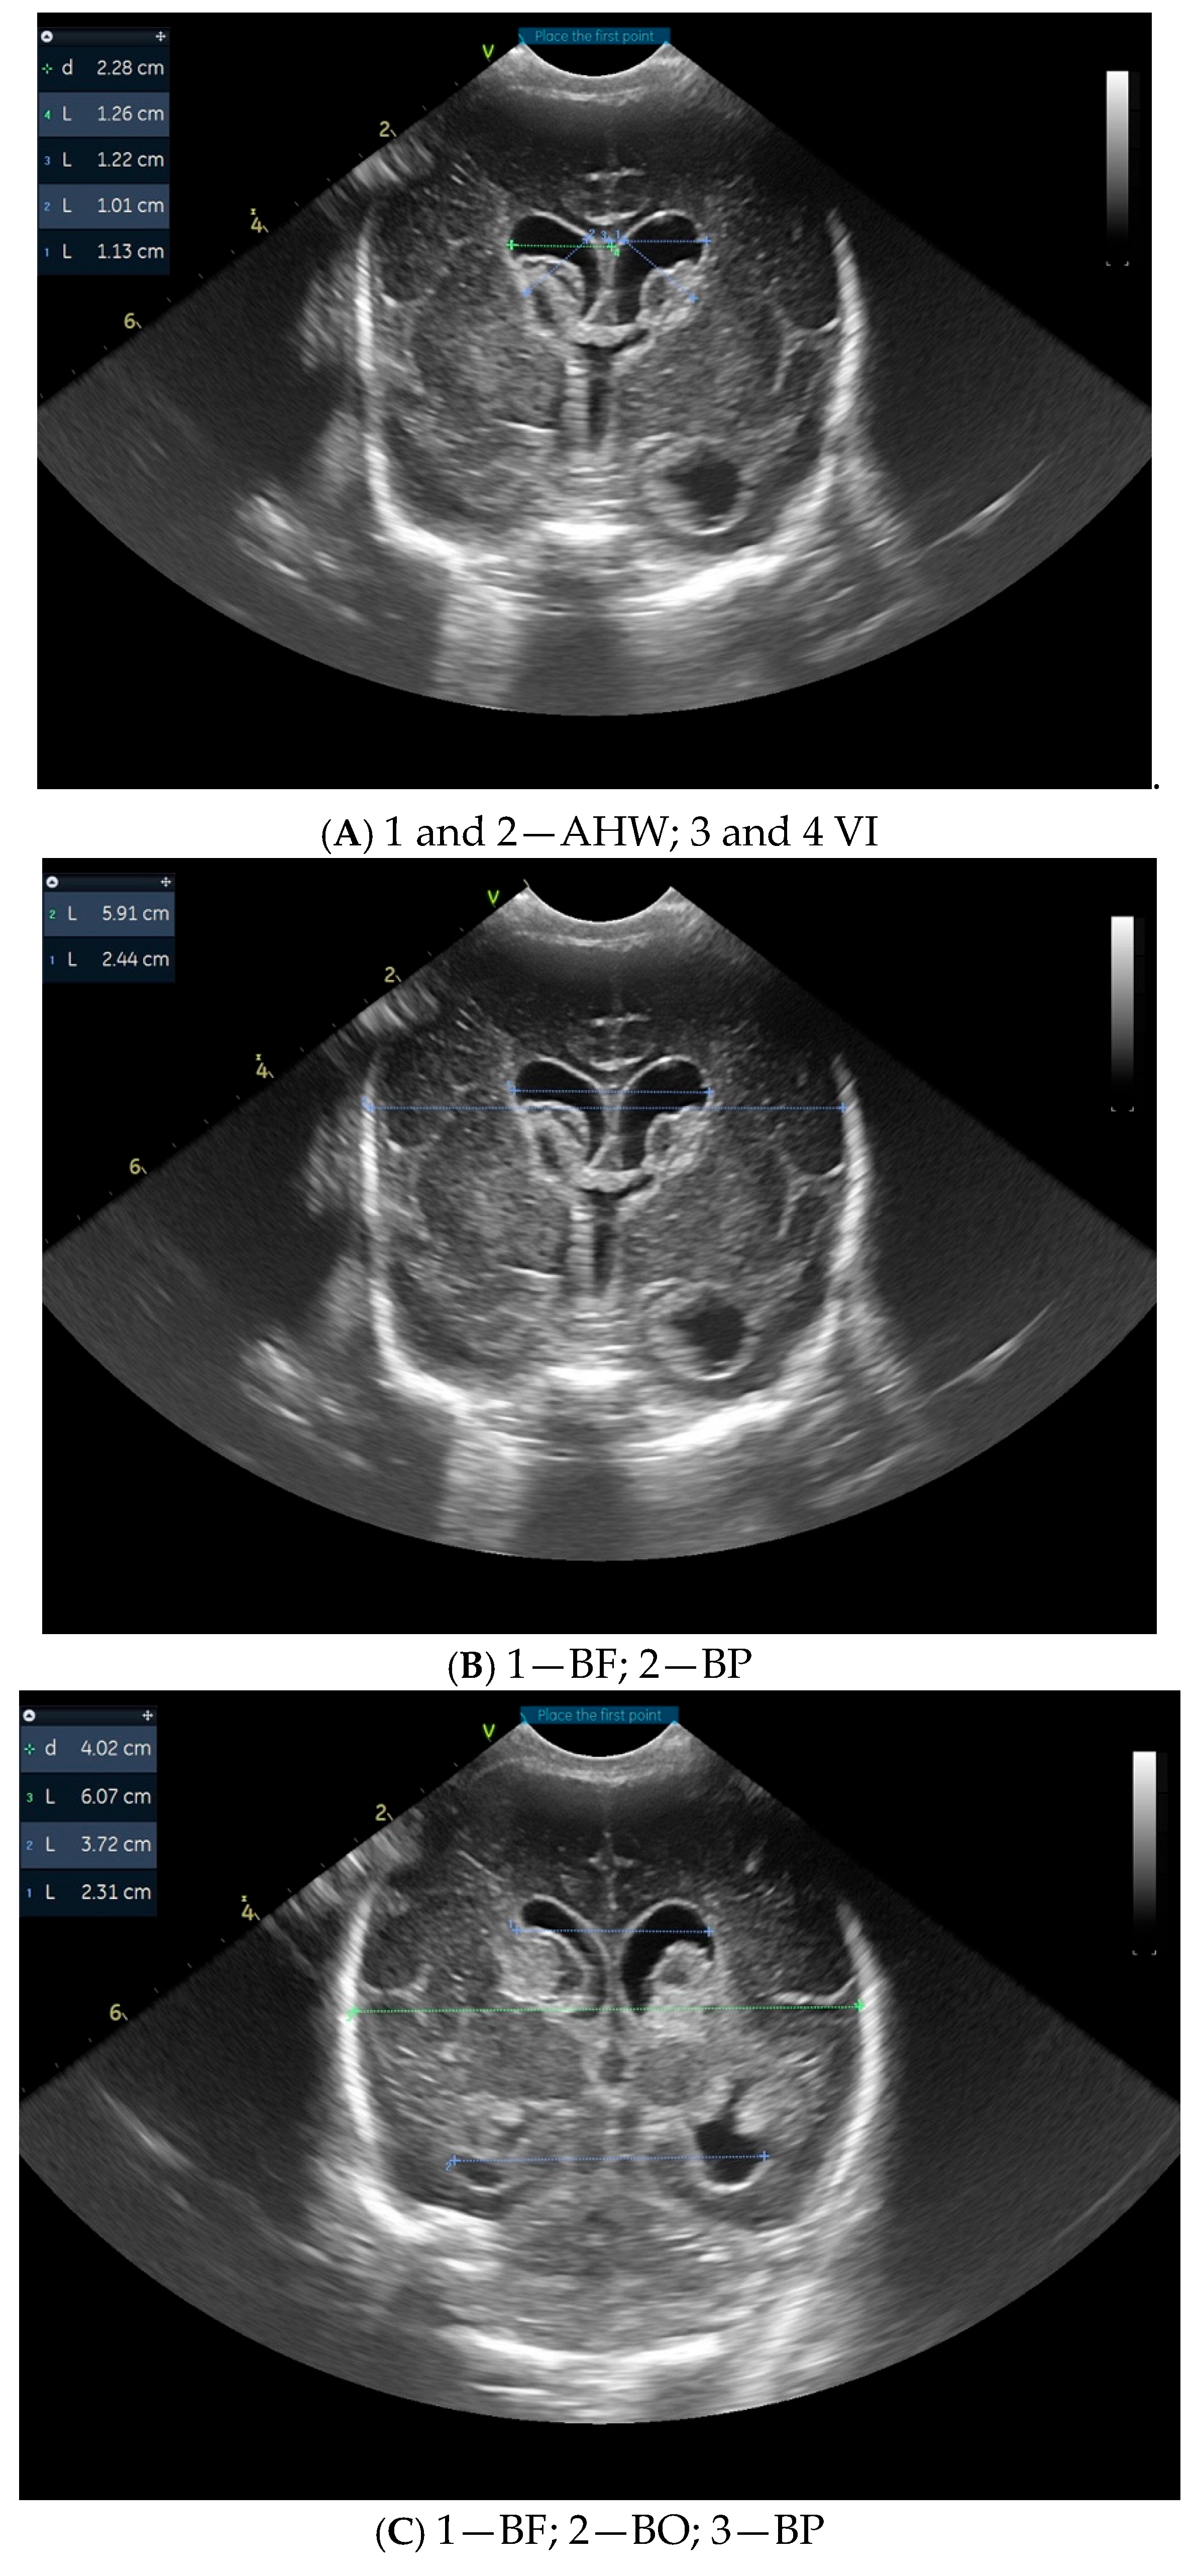

3. Results